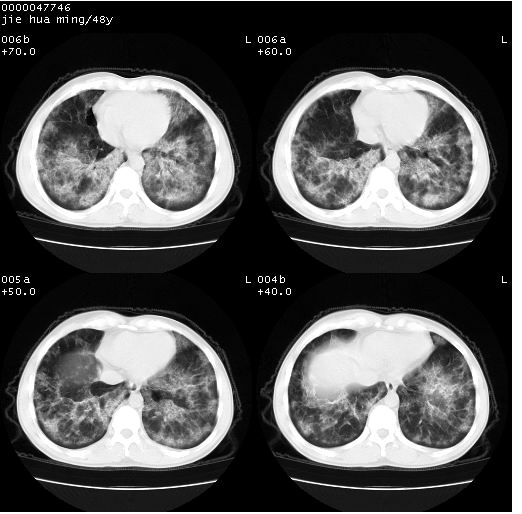

以下是引用dr.yang在2008-5-1 6:25:00的发言:[br]两肺广泛毛玻璃样的片状影,密度不均,边缘欠清,呈碎石路样改变,[br]考虑,1双肺间质性肺炎,2肺泡蛋白沉积症3支气管肺泡癌[br]

以下是引用hhcckk在2008-5-1 8:06:00的发言:[br]支持肺泡蛋白沉积症[br]依据:[br]1、病灶边缘清楚----地图征[br]2、病灶内部小叶间隔或小叶内间隔增厚所形成的网格状影----碎石路样表现[br]3、抗炎治疗无效(炎症抗炎治疗有效)[br]4、纵隔内未见肿大淋巴结(肺泡细胞癌时常有)[br][br]附肺泡蛋白沉积症资料[br][br]肺泡蛋白沉积症(pulmonary alveolar proteinosis)是一种原因不明的以肺泡腔内大量含脂糖蛋白样物质沉积为特征的疾病。[br]病理改变:(1)肺泡和细支气管腔内充满大量含脂糖蛋白样的粘稠物质,该物质为颗粒状或絮状的糖原pas染色阳性的磷脂蛋白。(2)肺泡壁及其间隔无异常改变。胸膜和淋巴结不受累及。(3)晚期可出现弥漫性肺间质纤维化。[br]临床表现:(1)好发年龄30~50岁,男性多于女性,偶见于儿童;(2)主要症状为呼吸困难、咳嗽、低热、消瘦、低氧血症和杵状指等。1/3的患者无症状。(3)实验室检查:痰液或肺泡灌洗液中可找到pas染色阳性颗粒物质。[br]hrct表现:肺泡蛋白沉积症具有特征性改变,即“碎石路样”表现(crazy-paving appearance,cpa)。主要包括(1)斑片状磨玻璃影:指肺野密度朦胧增加,内可见肺血管纹理影,系肺泡腔内充满低密度的磷脂蛋白物质所致。(2)其内部小叶间隔或小叶内间隔增厚所形成的网格状影,为小叶间隔水肿、肺泡壁内淋巴细胞和巨噬细胞浸润以及小叶内淋巴管扩张的缘故。(3)病灶边缘清楚,呈地图样分布于肺野外围或肺门及中央区。[br]

以下是引用zsl6918在2008-5-1 7:35:00的发言:[br]双肺磨玻璃样病变,可见铺碎路石征,病变区与正常区交错。边界清晰。符合肺泡蛋白质沉着征,高分辨扫描会更清楚漂亮。建议临床肺泡灌洗。

以下是引用yangyudong333在2008-5-1 5:36:00的发言:[br][br] 两肺广泛毛玻璃样的片状影,密度不均,边缘欠清,呈碎石路样改变,[br]考虑,1双肺间质性肺炎,2肺泡蛋白沉积症[br]